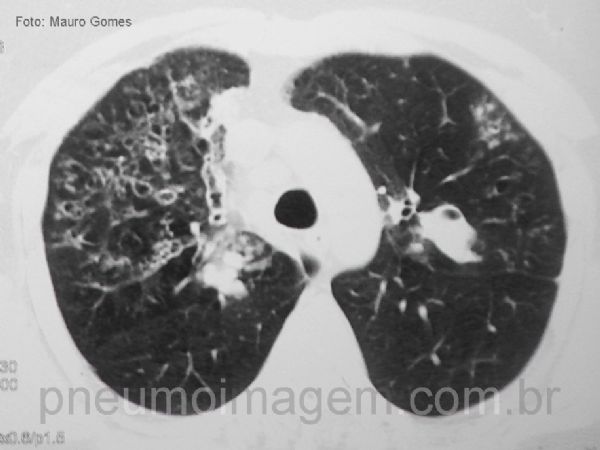

Neste corte observa-se as bronquiectasias centrais e o sinal do dedo de luva (seta amarela). Esse paciente apresentava IgE total de 16400, sorologia, prick-test e IgE RAST para Aspergillus positivos.

In this section we can observe the central bronchiectasis and the sign of the glove finger (yellow arrow). This patient had total IgE of 16400, serology, prick-test and RAST IgE for Aspergillus positive.